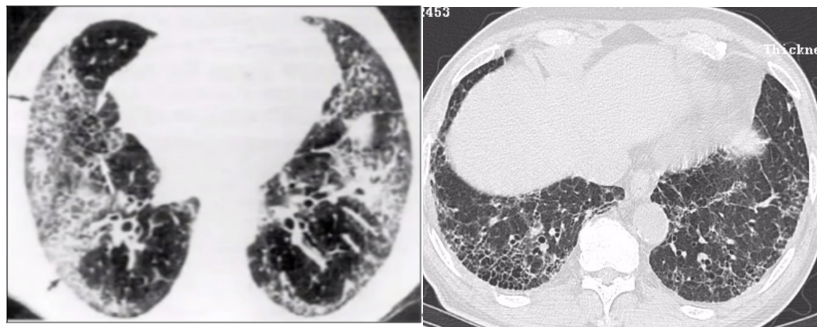

下图为ILD的基本影像学改变,如大片磨玻璃影、胸膜下实变影、蜂窝网格影等改变。

临床上主要通过临床表现、胸部影像学、实验室检查、支气管肺泡灌洗(BAL)等对AE-IPF进行诊断。①临床表现:1个月内,呼吸道症状(呼吸困难,咳嗽)恶化;②胸部影像学:HRCT表现,典型普通型间质性肺炎(UIP)型,基础上出现新的磨玻璃影和/或实变影,主要表现为3种类型—弥漫型、多灶型和周边型;③实验室检查:血细胞计数分类、脑钠肽(BNP)、肌钙蛋白、D-二聚体,C反应蛋白(CRP)和红细胞沉降率(ESR);病原体检查(分子生物学技术);④BAL:怀疑AE-IPF患者,需行BAL以评估肺部感染和恶性肿瘤;临床评估能够耐受支气管镜检查,或者肺功能一氧化碳弥散量(DLCO)≥30%预测值或吸氧后PaO2纠正到70 mmHg以上的患者;权衡利弊,建议谨慎考虑是否选择BAL检查;⑤肺活检:经支气管镜肺活检术(TBLB)小标本的病理诊断价值有限,可能引起病情加重,不建议。对怀疑AE-IPF患者的外科肺活检,手术风险高,可能加重患者病情,因此也不建议。

AE-IPF的诊断标准为:①通常在1个月内出现了临床上显著的急性呼吸困难加重;②胸部HRCT证实在UIP型改变基础上双肺新出现磨玻璃影和/或实变影;③排除心衰或液体负荷过重导致的呼吸功能恶化或急性肺水肿。